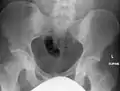

The radiographic appearance of osteopoikilosis on an X-ray is characterized by a pattern of numerous white densities of similar size spread throughout all the bones. This is a systemic condition. It must be differentiated from blastic metastasis, which can also present radiographically as white densities interspersed throughout bone. Blastic metastasis tends to present with larger and more irregular densities in less of a uniform pattern. Another differentiating factor is age, with blastic metastasis mostly affecting older people, and osteopoikilosis being found in people 20 years of age and younger.

Osteopoikilosis of the hips on CT.